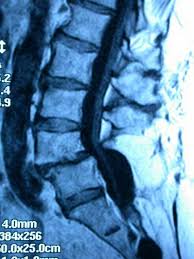

Hasta el momento, ningún estudio ha evaluado la dinámica de protuberancia del disco en función del grado de tropismo facetario. La importancia del aumento de disco como fuente de dolor lumbar está en continuo debate, en parte debido a la falta de criterios de medición estandarizados [13]. Si bien hay una alta prevalencia en individuos asintomáticos [14, 15], el abultamiento discal se ha asociado con desgarros anulares radiales [16] y dolor ciático reciente [17]. También se ha demostrado que la protuberancia del disco aumenta con la degeneración del disco [18].

El propósito de este estudio fue determinar si el grado de tropismo facetario se asoció con diferencias en la dinámica de protuberancia discal en los niveles L3-L4, L4-L5 y L5-S1 en pacientes sintomáticos, y cómo la edad afecta esta asociación mediante el uso cinético imágenes de resonancia magnética (kMRI)